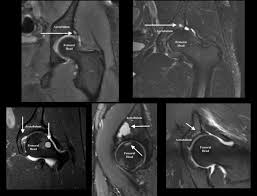

Bone Marrow Edema Syndrome Bmes Typical Signal Pattern Of Diffuse Download Scientific Diagram